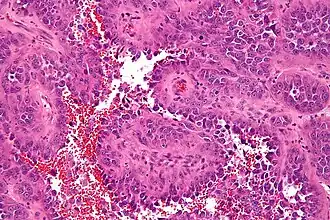

![]() Микрофотография ангиосаркомы. Окрашено гематоксилином и эозином. | |

Ангиосаркома представляет собой бугристую эластической консистенции опухоль, располагающуюся в глубине мягких тканей и инфильтрующую их. На разрезе состоит из полостей, заполненных кровянистым содержимым. Микроскопически опухоль состоит из большого числа тонкостенных кровеносных сосудов и обильного разрастания малодифференцированных полиморфных клеток. В одних случаях преобладают разрастания клеток типа эндотелия (гемангиоэндотелиома), в других — недифференцированные клетки разрастаются вокруг сосудов наподобие муфт (перителиома, перителиальная саркома)[1].